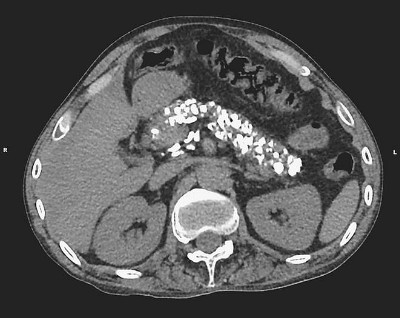

වෛද්යවරු රෝගියාගේ උදරයේ CT ස්කෑන් පරීක්ෂණයක් සිදු කළහ. එහිදී හෙළි වුනේ මේ පුද්ගලයාගේ ඇලදිව හෙවත් අග්න්යාශයේ (pancreas) බහුලව කැල්සියම් තැන්පත්ව ඇති බවයි. අග්න්යාශය කලක් තිස්සේ දැවිල්ල හට ගැනීමේ හේතුවෙන් නිදන්ගත අග්න්යාශ දාහයෙන් (chronic pancreatitis) පෙළෙන බව වෛද්යවරු නිගමනය කළහ. නිදන්ගත අග්න්යාශයෙන් පෙළෙන රෝගින්ගේ සාමාන්යයෙන් මේ ආකාරයට කැල්සියම් තැන්පත්වීම දැකිය හැකි වෙයි. එහෙත් මේ රෝගියාගේ දැකිය හැකි මට්ටමක කැල්සියම් තැන්පත් වීම දුර්ලබ සිද්ධියක් යයි රෝහලේ නේවාසික වෛද්ය දොස්තර යුබ්රාජ් සෙධායි පවසයි.

වසර ගණනාවක් තිස්සේ බෙහෙවින් මධ්යසාරය පානය කිරීම නිදන්ගත අග්න්යාශ දාහයට සුලබ හේතුව බව ජාතික සෞඛ්යායතන(National Institutes of Health) පවසයි. මධ්යසාරය හේතුවෙන් අග්න්යාශයේ සෛල හානියට පත් වීමට ඉඩ තිබේ. එමෙන්ම අග්න්යාශයේ පටක විනාශ කරන එන්සයිම වහනය කිරීමට ද මෙම සෛල උත්තේජනය කරවයි. ප්රදාහයට මග පාදන්නේ මෙය බව සෙධායි පෙන්වා දෙයි. ‘දිගු කාලයක් මධ්යසාරය පානය කිරීම අග්න්යාශයේ නිදන්ගත ප්රදාහයට තුඩු දෙනවා’ ඔහු කියයි. අග්න්යාශයේ චූර්ණීකරණය හෙවත් කැල්සීනීකරණයට හේතු වන්නේ ප්රදාහයට පත් අග්න්යාශ පටකයේ කැල්සියම් තැන්පත් වීමෙන් බව ඔහු පෙන්වා දෙයි. (කැල්සියම්, රුධිර ධාරාව ද ඇතුළත්ව ශරීරය තුළ ස්වභාවිකව පවතී. එහෙත්, හාර්වඞ් වෛද්ය විද්යාලය පෙන්වා දෙන අන්දමට කෙනෙකුගේ රුධිරයෙහි ඇති කැල්සියම් සාමාන්ය මට්ටමක පැවතියත් සිරුරේ පටක හානියක් ඇති තැන්වල කැල්සියම් තැන්පත් වේ).